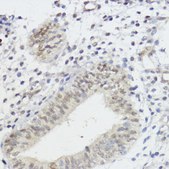

IF, IHC, IP, WB

immunofluorescence: 1:50-1:100, immunohistochemistry: 1:50-1:100, immunoprecipitation (IP): 1:50-1:200, western blot: 1:500-1:2000